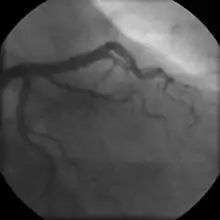

Coronary angiogram of a female

For symptomatic people, stress echocardiography can be used to make a diagnosis for obstructive coronary artery disease.[68] The use of echocardiography, stress cardiac imaging, and/or advanced non-invasive imaging is not recommended on individuals who are exhibiting no symptoms and are otherwise at low risk for developing coronary disease.[68][69]